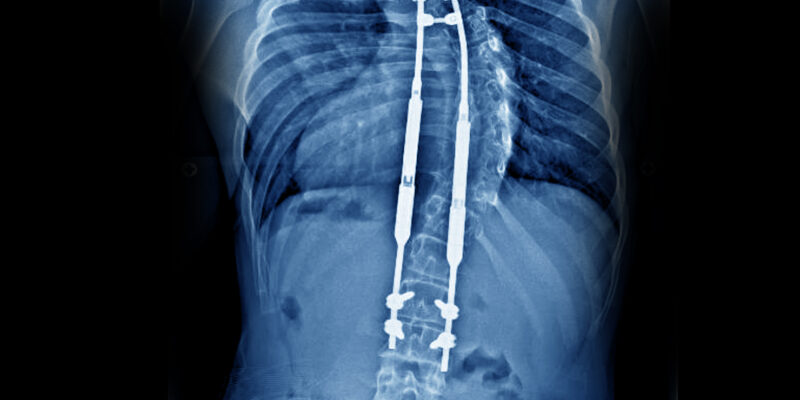

Growing rods are metal rods attached to the spine in an operation, that allow for continued growth of the spine. They are effectively an internal brace system to stabilise the spine, providing partial correction and stopping the curve from progressing. The rods are put in from the back of the spine and attached to the spine above and below the curve. The curve is partially corrected during the first operation.

The child returns every six months to a year to have the rods lengthened to keep up with the natural growth of the spine, whilst directing the growth into a more ‘normal’ line. This is a smaller operation, under general anaesthetic, and the child is usually in hospital just one or two nights.

When the child becomes older and reached their growth potential, the growth rods will be removed and the surgeon will perform a spinal fusion operation.